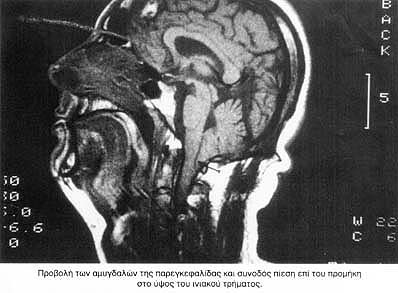

Από τις νευροαπεικονιστικές μεθόδους η αξονική τομογραφία εγκεφάλου με εμπλουτισμό, έδειξε εκτασία της αριστερής σπονδυλικής ενώ η τομογραφία με μαγνητικό συντονισμό έδειξε:

α. Ελάττωση του βάθους του οπισθίου κρανιακού βόθρου.

β. Προβολή των αμυγδαλών της παρεγκεφαλίδας δια μέσου του ινιακού τρήματος το κατώτερο σημείο των οποίων φθάνει μέχρι το οπίσθιο τόξο του Α1, σπονδύλου. Υπήρχε συνοδός πίεση επί του προμήκη στο ύψος του τρήματος.

Τα ανωτέρω ευρήματα συνηγορούν υπέρ δυσπλασίας Arnold-Chiari τύπου Ι.